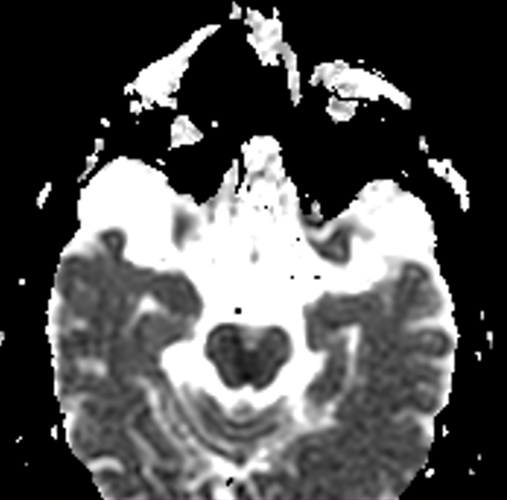

TAC de cráneo simple sin lesiones agudas, RM cerebral con imagen hiperintensa en difusión, hipointensa en ADC e hiperintensa en FLAIR a nivel de tegmento mesencefálico medial (ver imagen 2), compatible con infarto mesencefalico en etapa subaguda, no candidata a trombolisis, se realizaron estudios de factores de riesgo cardiovascular sin hallazgos significativos, se dio egreso con prevencion secundaria.

Imagen 2. RM cerebral en secuencia difusión, ADC y FLAIR